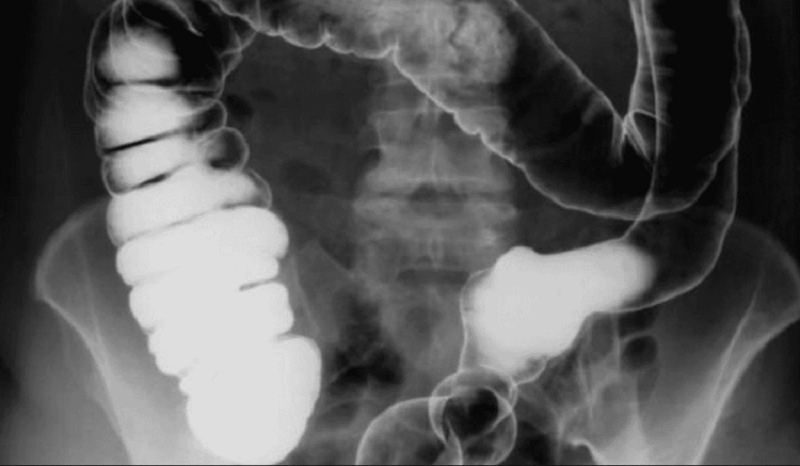

5. Chụp X-quang có thuốc cản quang

Phương pháp này giúp bác sĩ quan sát hình dạng dạ dày và các bất thường lớn một cách trực quan. Bằng cách bao phủ niêm mạc dạ dày bằng dung dịch cản quang, hình ảnh X-quang sẽ làm nổi bật các ổ loét, khối u hoặc hẹp môn vị, hỗ trợ chẩn đoán sơ bộ trước khi quyết định nội soi.

- Nguyên lý: Người bệnh uống dung dịch Barium, thuốc bao phủ niêm mạc và làm nổi bật hình dạng dạ dày dưới tia X.

- Ứng dụng: Phát hiện loét sâu, khối u, hẹp môn vị hoặc thay đổi nhu động dạ dày.

- Hạn chế: Không phát hiện tổn thương nhỏ, ít phổ biến hơn nội soi.

- Phương pháp: Chụp X-quang có cản quang, siêu âm, CT Scan hoặc MRI.

- Phương pháp: Chụp X-quang có cản quang, CT Scan, MRI.